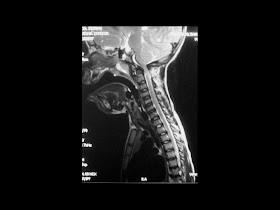

A 32-year-old man presented with a 6-month history of severe headaches, hemiparesis on the left side, and impaired hearing in the left ear. His medical history was otherwise unremarkable.